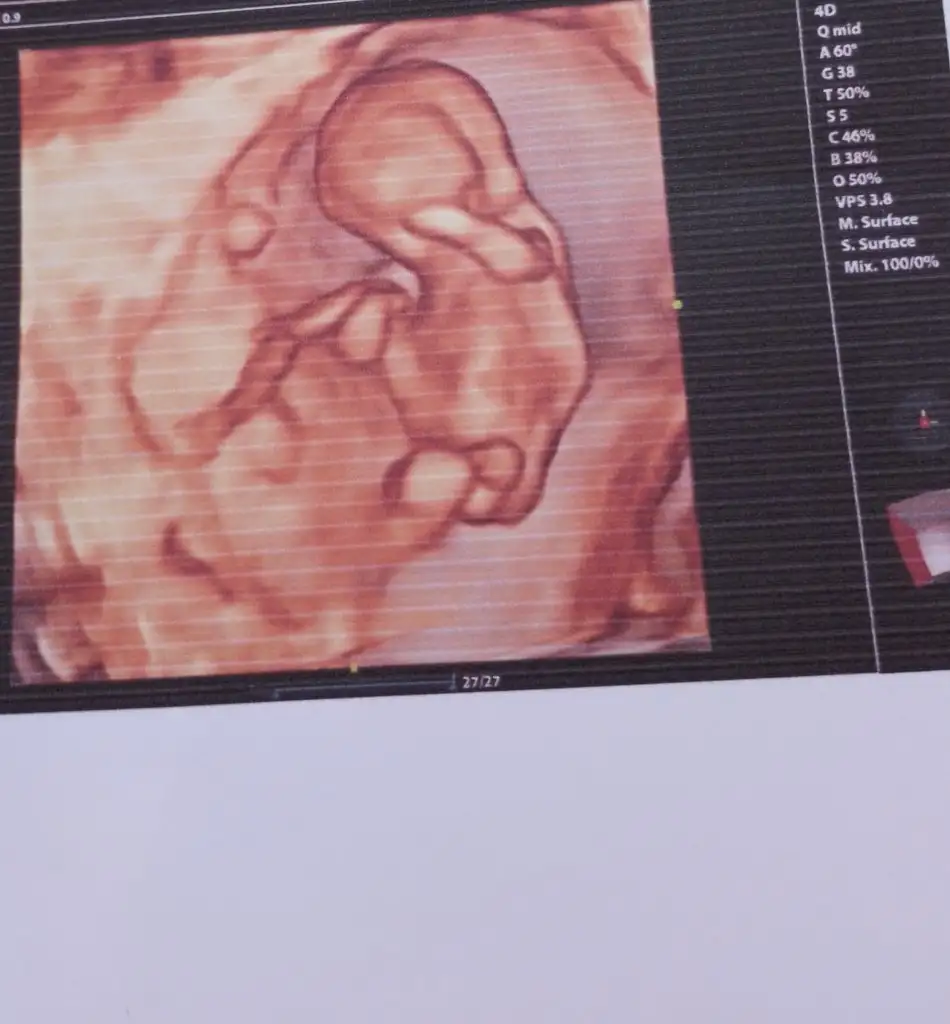

11 haftlik halii erkek demisdin dha beli deil doktor tahminm var dedi ama erkn 2 hafta sonra kesin soyliycm sna dedi 3 aylik olucaz .. erkn ogrncem cinsyti acaba erkek oldu icin mi erkn . Digr kizlrm 5 ve 6 ayda beliydiBu kesinlikle erkek

Valla ben bilmem. Anlamam da. Ama çok erken. 17.haftaya kadar kız dediler sonra erkek oldu bizim. Kim ne derse desin inanmayın.11 hafta simdi sizce nedr

Anldmm tskr .. canm doktr da bana iki hafta sonra gel dedi kesin soylicem dedi . 11 haftyz suan acaba bukdr erkn soylemsi erkek olablrmi kizlrin gec belli oluyoValla ben bilmem. Anlamam da. Ama çok erken. 17.haftaya kadar kız dediler sonra erkek oldu bizim. Kim ne derse desin inanmayın.

Evet o zaman erkek görmüş olabilir ama sadece tahmin. Bizim oğluşun pipisi gözükmedi 17 ye kadar. 2 hafta sonra söylemesi de çok güvenli olmaz ama renkli ultrasonu varsa kesin görürAnldmm tskr .. canm doktr da bana iki hafta sonra gel dedi kesin soylicem dedi . 11 haftyz suan acaba bukdr erkn soylemsi erkek olablrmi kizlrin gec belli oluyo